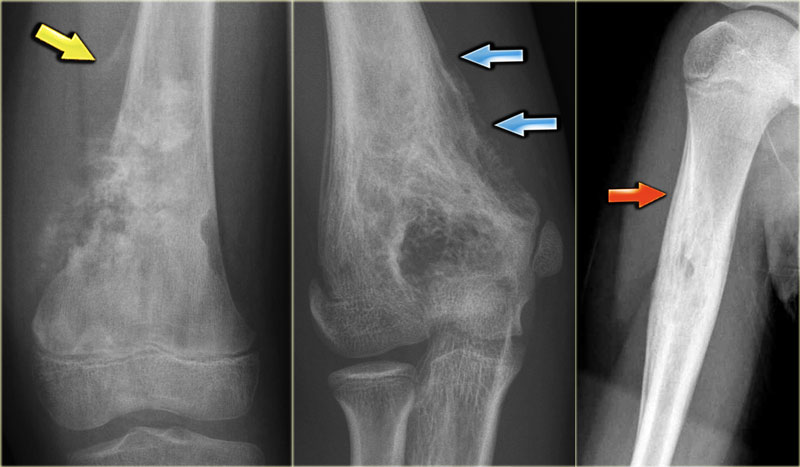

При диагностике остеосаркомы собак поражающей скелет, первым методом обследования является качественное радиографическое обследование животного.

Общие отклонения на снимках при остеосаркоме заключаются в почти полном лизисе кости в зоне поражения совместно с остеобластическими и остеокластическими изменениями различной степени выраженности на периферии. Радиографическими особенностями остеосаркомы кости являются выраженный лизис кортикального слоя (вплоть до патологических переломов), формирование новой кости вокруг опухоли (типа вспышки солнца) с приподнятием надкостницы и значительное увеличение объема окружающих мягких тканей. На ранних этапах развития опухоли, радиографические изменения могут заключаться в потере ясного трабекуллярного паттерна метафиза и размытии переходной зоны в месте локализации опухоли. Радиографические изменения остеосаркомы собак зависят от размера, гистологического подтипа, локализации и времени развития опухоли. Радиографические признаки остеосаркомы сходны с таковыми при остеомиелите, особенно грибковом. Радиографические изменения при остеосаркоме кошек сходны с таковыми при остеосаркоме собак.

Поражение аппендикулярного скелета при остеосаркоме собак отмечается в ¾ случаев (75%), и лишь ¼ (25%) всех случаев опухоли приходится на поражение аксиального скелета. Характерная локализация опухоли при поражение аппендикулярного скелета – метафиз длинных костей, при этом, передние конечности поражаются в два раза чаще задних. На передних конечностях характерным местом локализации остеосаркомы собак является дистальный отдел лучевой кости и проксимальный отдел плечевой кости.

Локализация остеосаркомы собак возле локтевого сустава отмечается крайне редко (поражение дистального отдела плечевой и проксимального отдела лучевой костей). На задних конечностях, излюбленным местом локализации остеосаркомы собак является дистальный отдел бедренной кости, проксимальный отдел голени, и дистальный отдел голени, развитие опухоли в данных участках примерно одинаково по частоте. Первичная остеосаркома собак с локализацией дистально к запястному и скакательному суставу отмечается достаточно редко. Локализация опухоли не оказывает какого либо влияния на прогноз заболевания. В одном описании 116-ти случаев первично остеосаркомы аксиального скелета, локализация поражений распределилась следующим образом: нижняя челюсть – 27%, верхняя челюсть – 22%, позвоночник – 15%, череп – 14%, ребра 10%, носовая полость и параназальные синусы – 9%, таз – 6%.

Рентгенограмма, иллюстрирующая остеосаркому дистального отдела лучевой кости (OSA)